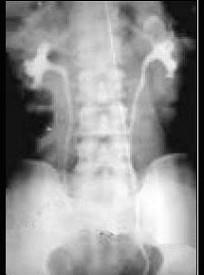

问题 女,56岁,间歇性无痛肉眼血尿1年余。体检:左腰部触及包块,表面不光滑,质较硬,膀胱镜检查左输尿管口喷血。应考虑 ( )

选项 A、多囊肾 B、肾结石伴积水 C、肾母细胞瘤 D、肾癌 E、肾盂肿瘤

答案 D